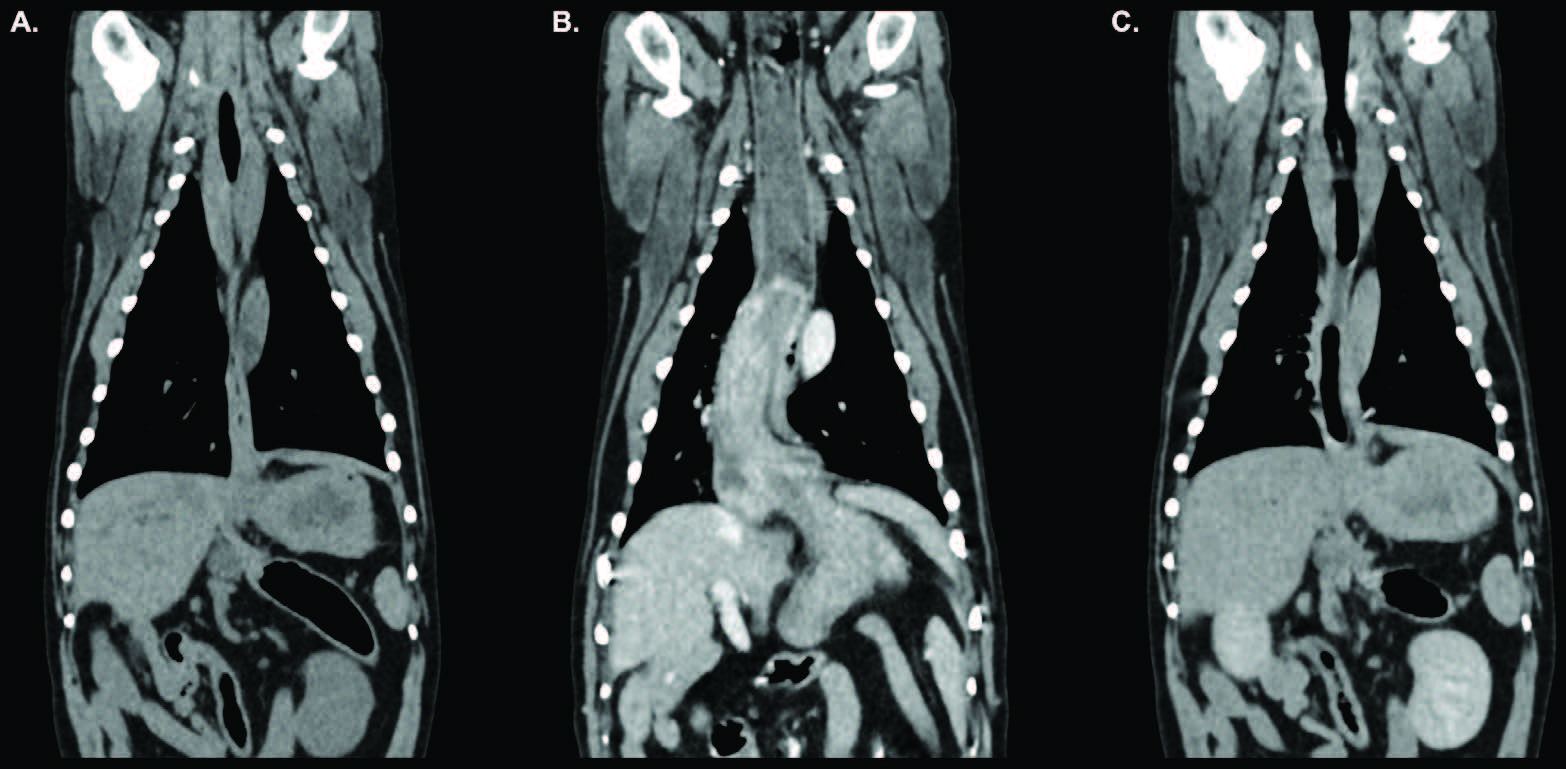

为进一步明确超声所见病变并寻找潜在转移灶,行头、胸、腹部增强CT检查。平扫示胃位置正常;静脉期增强扫描见胃底经食管裂孔向前疝入远段食管腔(图1-2)。远段食管壁部分包绕胃底,横断面呈“靶征”(图3)。食管前段含少量至中等量混杂密度液-软组织物质。延迟期图像显示胃已回纳至正常解剖位置。

图2. 检查过程中获得的胸廓和腹腔前部的背侧重建图像,分别显示平扫期(A)、静脉期(B)和延迟期(C)。在平扫期(A)和延迟期(C)图像中,胃位置正常,食管扩张不明显。在静脉期(B)图像中可见胃食管套叠,具体标注见图1。

胃部改变符合一过性、可自行复位的胃-食管套叠(GEI)。可能为单次、自发性GEI,或由碘海醇诱发恶心、麻醉致下食管括约肌松弛或两者共同触发;亦可能为偶然捕捉到的慢性、间歇性GEI,与静脉对比剂或麻醉无关。若属后者,该套叠可为既往滑动型食管裂孔疝的进展/加重,或为一独立、并发、间歇发生的疾病实体。